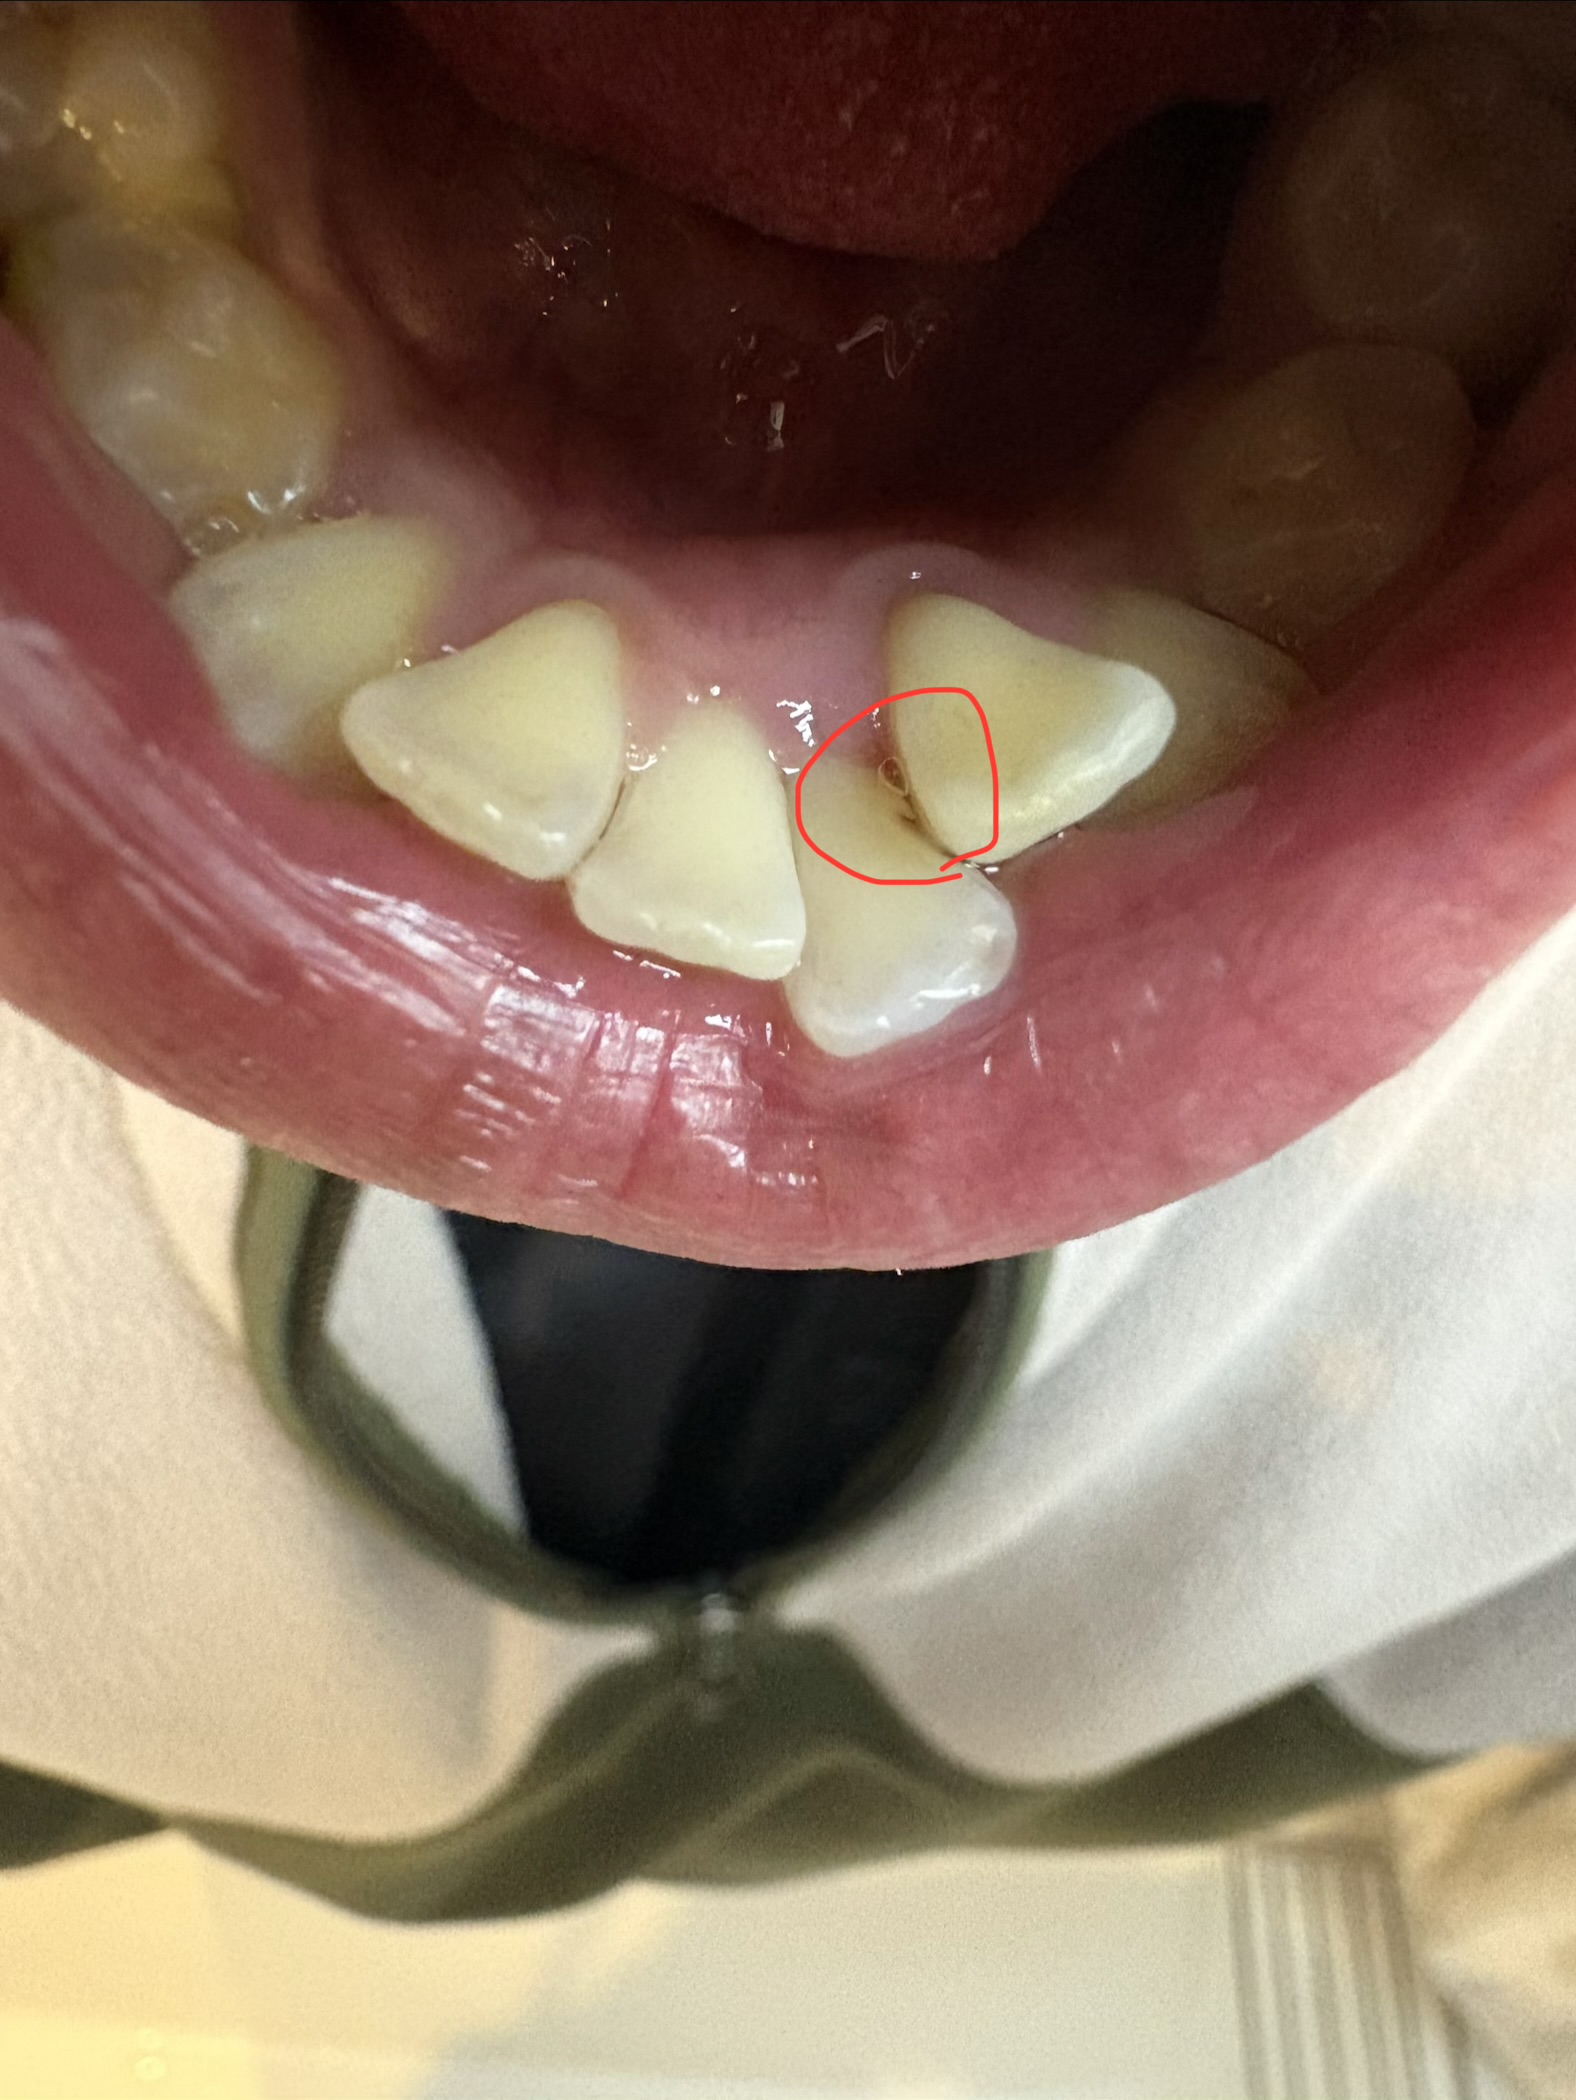

マウスピース矯正中、差し歯にしていた前歯の歯根が折れてしまいました。